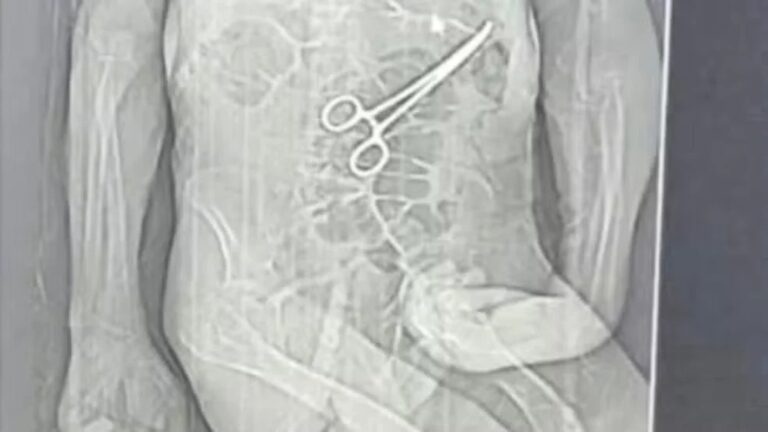

Um homem de 68 anos morreu na véspera do Natal após passar por duas cirurgias no Hospital Municipal de João Pinheiro, no noroeste de Minas Gerais. A família de Manoel Cardoso de Brito acusa a unidade de saúde de erro médico, afirmando que uma pinça cirúrgica foi esquecida dentro do corpo do paciente durante o primeiro procedimento.

A Secretaria Municipal de Saúde confirmou que um corpo estranho foi identificado e retirado durante uma segunda cirurgia e informou que foi aberta uma sindicância administrativa para apurar o caso.

Somente após a morte, a família teve acesso a uma tomografia divulgada por uma rádio local, que indicaria a presença de uma pinça cirúrgica no abdômen do paciente. O advogado da família, Iuri Evangelista Furtado, informou que irá solicitar todos os prontuários, laudos, exames e registros clínicos e administrativos do hospital para acompanhar as investigações.

Em nota oficial, a Secretaria Municipal de Saúde afirmou que Manoel deu entrada no hospital em estado grave, com infecção instalada, idade avançada e diversas comorbidades, como cardiopatia, diabetes, arritmia cardíaca e sequelas de AVC. A pasta confirmou a retirada do corpo estranho durante a reabordagem cirúrgica, informou que comunicou o caso à Anvisa, reforçou protocolos de segurança do paciente e abriu sindicância para apuração dos fatos.